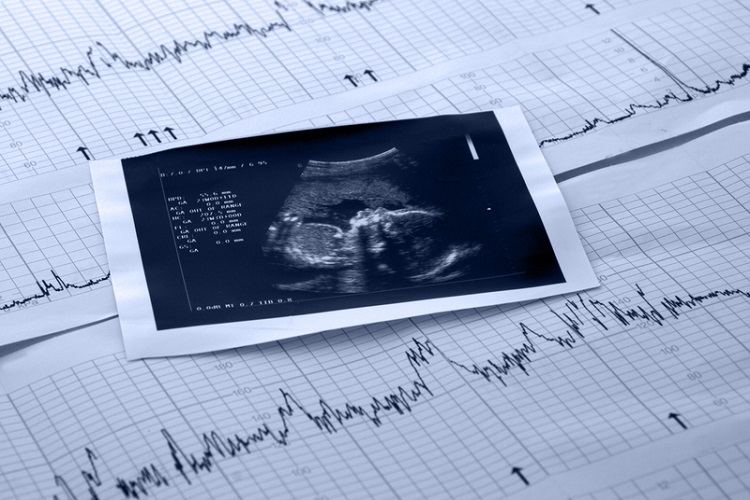

變性網紅「罔腰」在IG公布懷孕訊息,同時放上醫院檢疫單與超音波照片,但罔腰是男轉女變性人,沒有子宮無法懷孕,而罔腰男友強調是接受某醫師「人體試驗」。對此衛福部次長批評妖言惑眾,下午指揮中心遭問回應道,將確認有無違法。